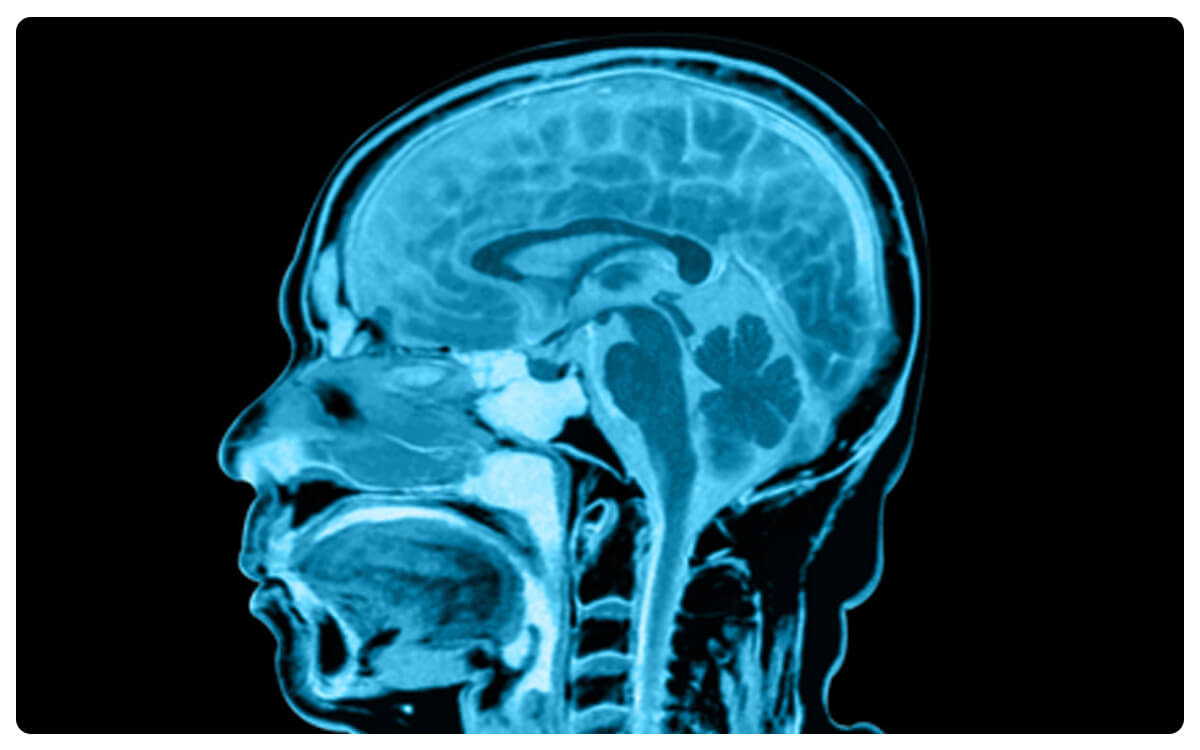

La Angio Tomografía Craneal, una técnica radiológica avanzada, emerge como una herramienta esencial en la exploración detallada y no invasiva de las estructuras vasculares en el cráneo y el cerebro. A través de la tomografía computarizada y la administración de un medio de contraste intravenoso, esta técnica permite la generación de imágenes tridimensionales de alta resolución que revelan la arquitectura vascular intracraneal y posibles anomalías vasculares.

La Angio Tomografía Craneal desempeña un papel crucial en el diagnóstico y seguimiento de enfermedades vasculares cerebrales, como aneurismas, malformaciones arteriovenosas y estenosis, brindando información valiosa para la detección temprana de complicaciones y la toma de decisiones clínicas informadas en el cuidado de la salud cerebral.